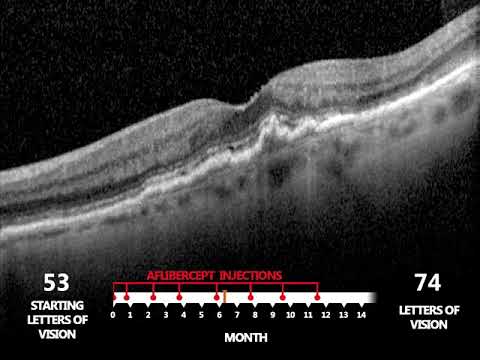

Altersbedingte Makuladegeneration: wie verläuft eine Injektionstherapie bei der feuchten AMD?

Altersbedingte Makuladegeneration: welche Medikamente gibt es für die feuchte AMD?